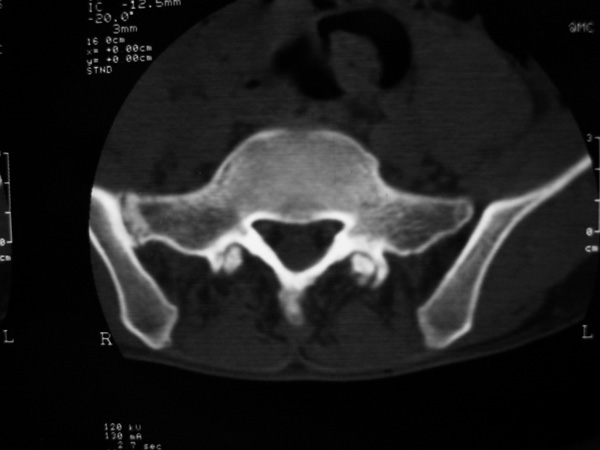

以下是引用w_jianhua在2007-3-8 11:14:00的发言:[br]椎小关节及右侧骶髂关节关节面毛糙,间隙不规则狭窄,骨皮质增生硬化,支持强直性脊柱炎,并椎间盘膨出

以下是引用fumaogui在2007-3-8 8:40:00的发言:[br]腰椎椎间关节增生硬化,关节间隙变窄,右侧骶髂关节间隙变窄,关节面硬化[br]考虑强直性脊柱炎.建议结合化验查:c--反应蛋白和类风湿因子.